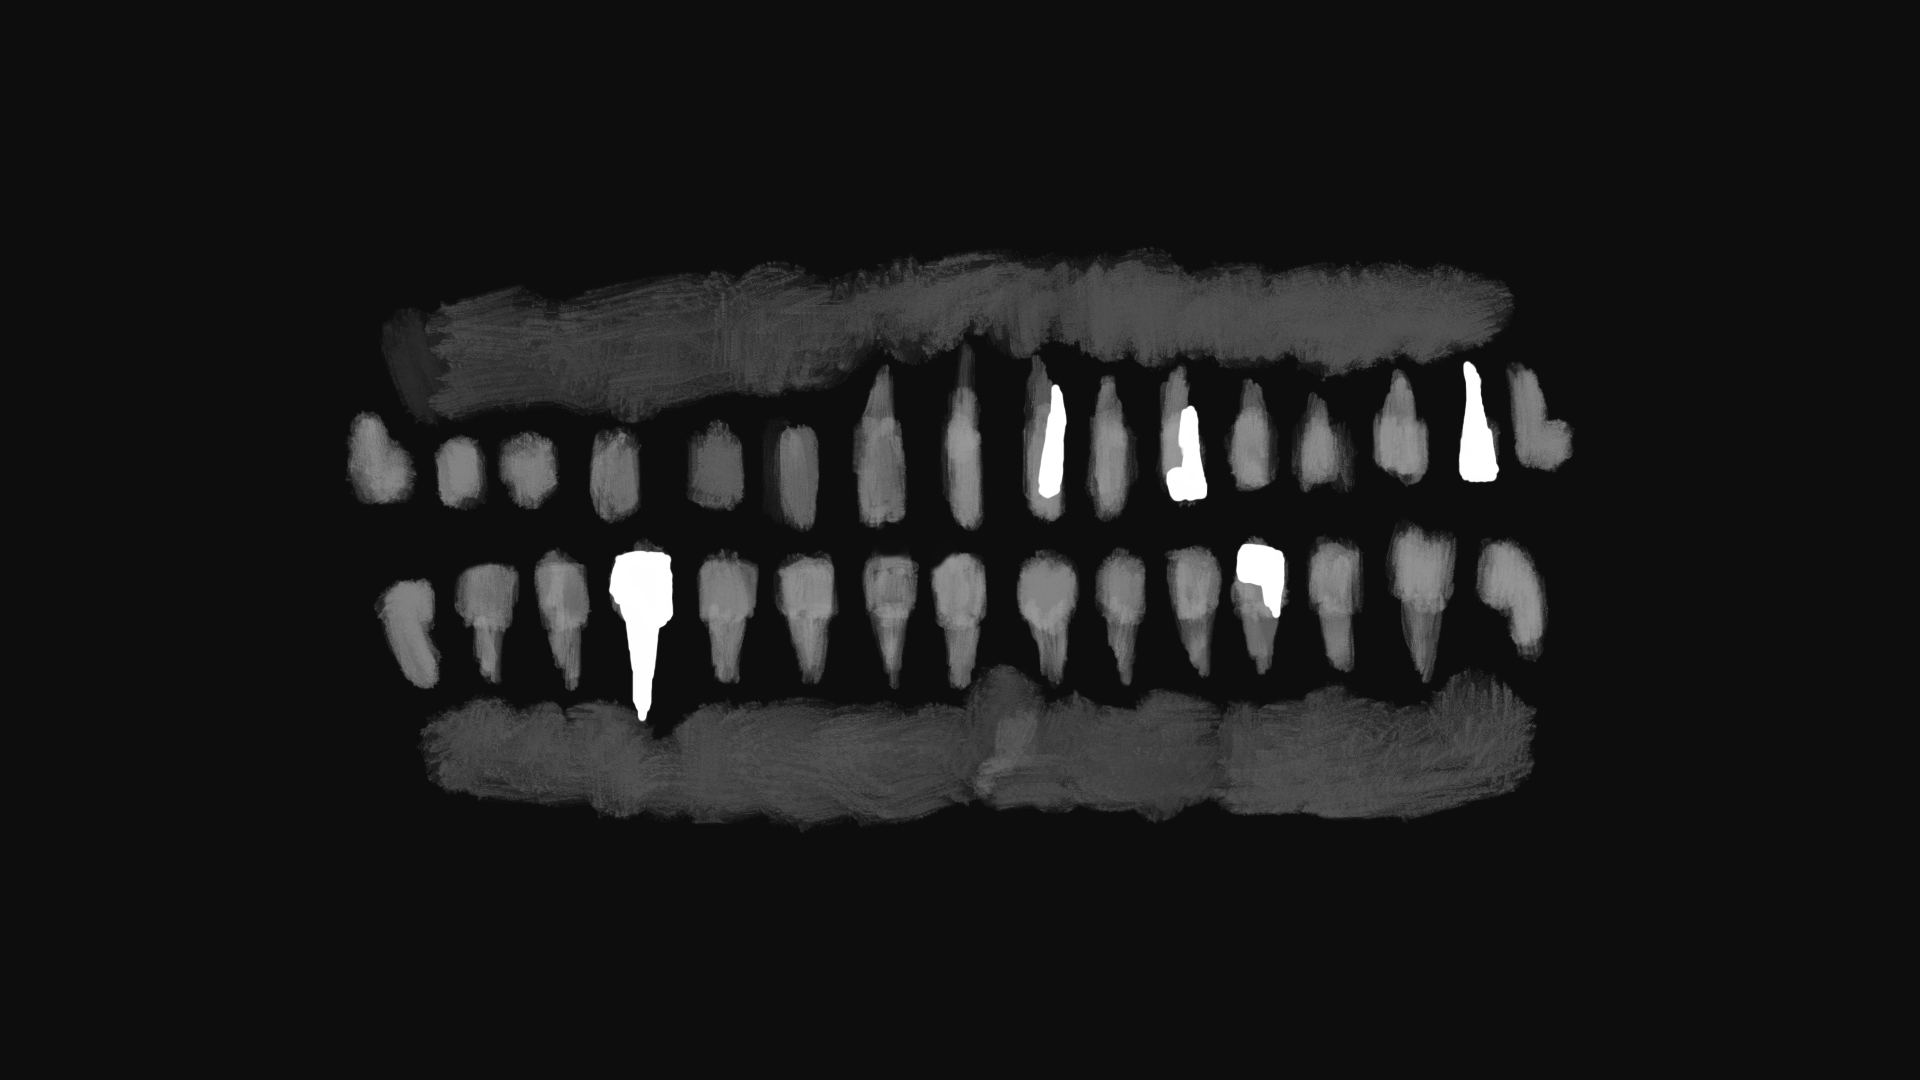

6本の死んだ歯

改めて後悔するボロボロの歯

奥歯が痛み久しぶりに歯医者に行きました。自分の歯のレントゲン写真を見て、壊滅的な歯の状態に今更、後悔しています。

よくよく数えると神経を抜いた歯が6本もあり、虫歯で削った歯を含めると、ほぼすべての歯が魔改造されており、よくもまあこんなになるまで放ったらかしていたなあ?と呆れるばかりです。